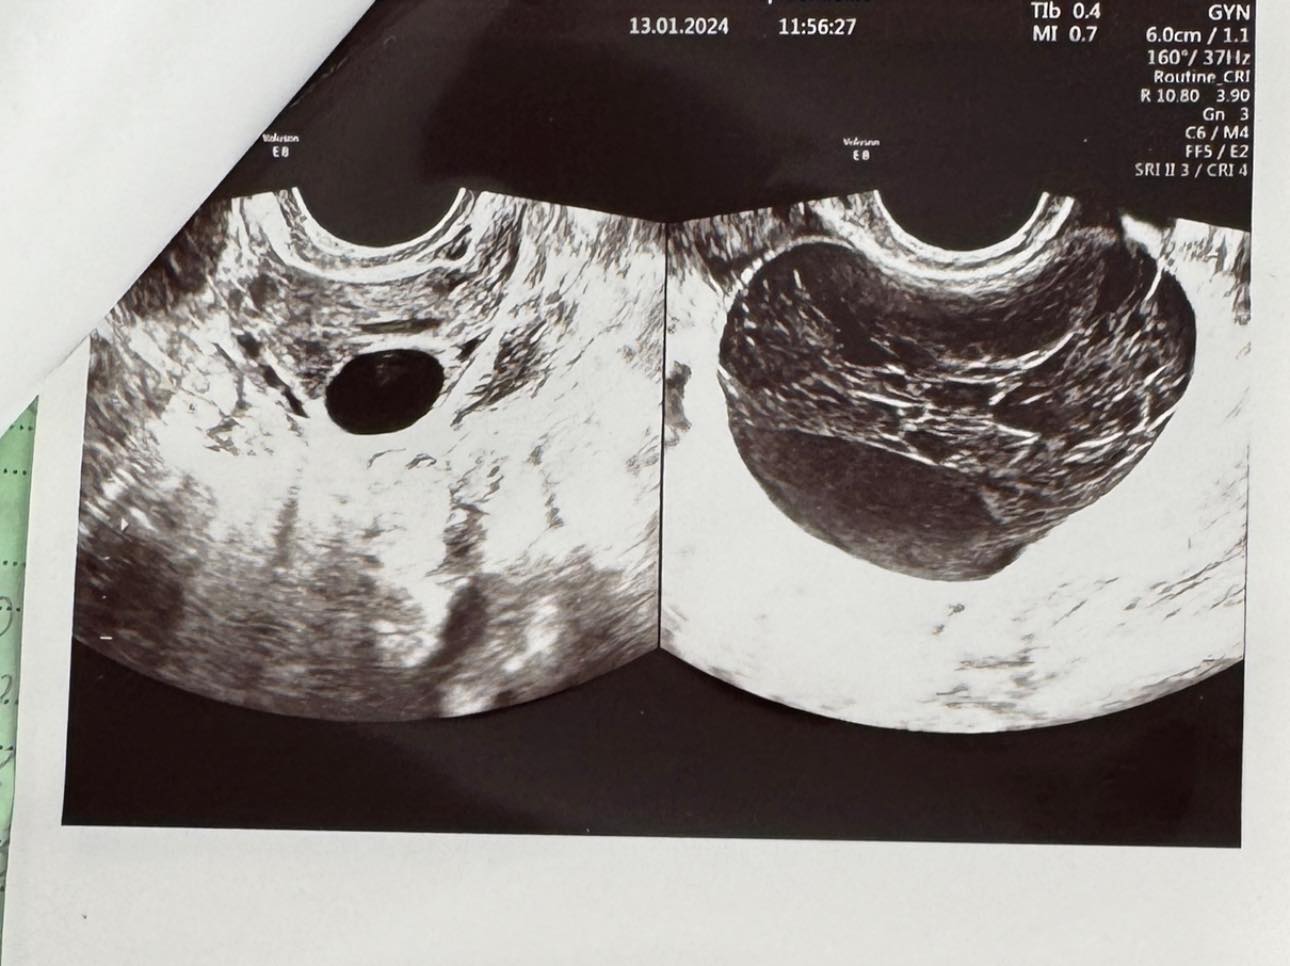

O tânără de 21 de ani a mers la medic din cauza unor dureri și a dereglărilor menstruale și a avut un șoc. A aflat că are un chist hemoragic de cm la nivelul ovarului drept. Aceasta a mers la medicul Alexandra Ciobanu, în luna ianuarie, cu „dereglări ale ciclului menstrual și dureri pelvine”.

Doctorul i-a dat să urmeze un tratament pentru cinci luni, pe care aceasta l-a urmat cu strictețe, iar rezultatele nu au întârziat să apară.